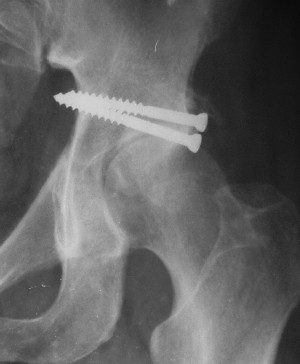

Послеоперационный снимок прямой 5/05/03

|

Послеоперационный снимок боковой 5/06/03

Больной 18 мая 2003 года в автоаварии получил перелом левой вертлужной впадины, вывих бедра. Госпитализирован в один из стационаров области.Вывих вправлен. В последствии бедро вывихивалось еще дважды. На консультацию был представлен снимок от 19.05.03г., больной переведен к нам 3.06.03г. Снимок при поступлении - перелом впадины, задне-верхний вывих бедра. 05.06.2003 г. выполнено открытое вправление вывиха левого бедра и остеосинтез стенки вертлужной впадины двумя винтами. Послеоперационный период без осложнений. Объем движений в левом тазобедренном суставе восстановился полностью. Выписан на амбулаторное лечение в удовлетворительном состоянии с рекомендациями 3 месяца ходить на костылях без нагрузки на оперированную конечность. На контрольных рентгенограммах левого тазобедренного сустава 13.10.2003 г. - признаки консолидации перелома; плотность, форма головки и состояние суставных поверхностей удовлетворительные. Разрешена дозированная осевая нагрузка, на конечность с использованием дополнительной опоры. 19.12.2003 г. больной обратился с жалобами на боли в левом тазобедренном суставе. На рентгенограммах левого тазобедренного сустава 19.12.2003 г., 20.02.04г. - асептичекий некроз головки бедра. 5.04.04г. - эндопротез. Сейчас ходит без трости, не хромает. Особенность эндопротезирования - при удалении винтов прослежена линия перелома заднего края впадины и предложено установить чашку несколько меньшего диаметра, чтобы она была покрыта несломанной частью.